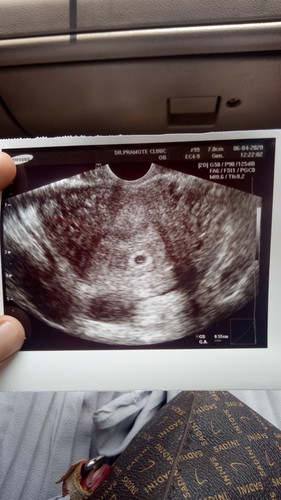

เราพึงไปซาวล์มาซาวล์ผ่านหน้าท้องไม่เจอน้องเลยตัดสินใจซาวล์ผ่านช่องคลอดเลยเจอตามรูปเลยค่ะ หมอบอกว่าเล็กมาจนเครื่องไม่สามารถวัดอายุครรภ์ได้ และก็ยังไม่ให้ฝากท้องหมอนัดอีกรอบปะมานสิ้นเดือน ควรเปลี่ยนหมอดีไหมค่ะ